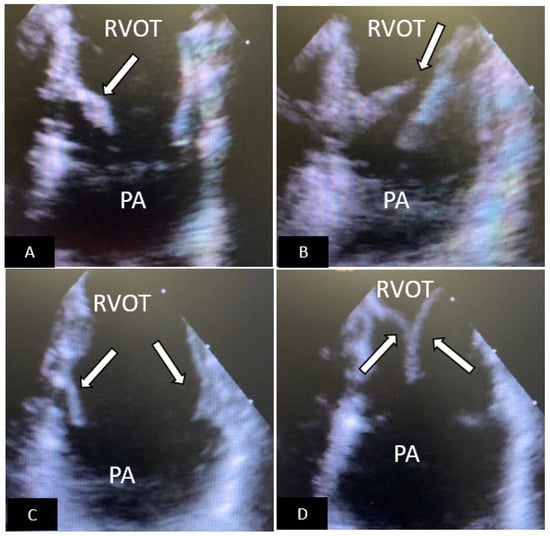

- Jone, P.N.; Ross, M.M.; Bracken, J.A.; Mulvahill, M.J.; Di Maria, M.V.; Fagan, T.E. Feasibility and Safety of Using a Fused Echocardiography/Fluoroscopy Imaging System in Patients with Congenital Heart Disease. J. Am. Soc. Echocardiogr. 2016, 29, 513–521. [Google Scholar] [CrossRef]

- Jone, P.N.; Haak, A.; Ross, M.; Wiktor, D.M.; Gill, E.; Quaife, R.A.; Messenger, J.C.; Salcedo, E.E.; Carroll, J.D. Congenital and Structural Heart Disease Interventions Using Echocardiography-Fluoroscopy Fusion Imaging. J. Am. Soc. Echocardiogr. 2019, 32, 1495–1504. [Google Scholar] [CrossRef] [PubMed]

- Hadeed, K.; Hascoët, S.; Karsenty, C.; Ratsimandresy, M.; Dulac, Y.; Chausseray, G.; Alacoque, X.; Fraisse, A.; Acar, P. Usefulness of echocardiographic-fluoroscopic fusion imaging in children with congenital heart disease. Arch. Cardiovasc. Dis. 2018, 111, 399–410. [Google Scholar] [CrossRef] [PubMed]